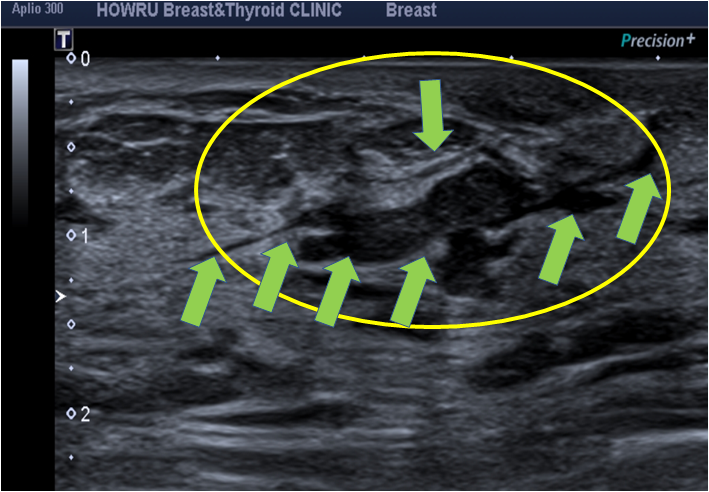

먼저 관내유두종은 유두와 연결된 유관 내부에 용종이 생기는 양성질환이다. 혹이 유두처럼 생겼다고 해서 유두종이라고 부르는데, 크기가 0.5cm 미만, 때로는 1cm 이상으로 매우 작게 발생합니다. 유방의 유두병변은 유두상 모양을 특징으로 하는 병변으로 고립성 유두종, 다발성 말초유두종, 유두종증 등이 있다. 유방암과 양성 유두병변 사이에는 직접적인 관계는 없으나 동시에 발생하거나 차후에 발생하는 유방암이다. 와 관련이 있습니다. 관내 유두종의 비교 유두종에는 일반적으로 단일성 관내 유두종과 다발성 말초 유두종이 포함됩니다. 고립성 관내 유두종은 유두 병변 중에서 가장 흔하며 35~55세의 폐경기 여성에서 가장 자주 발생합니다. 다발성 말초 유두종은 고립성입니다. 유관내 유두종보다 어린 나이에 발생하며, 유두 분비물이 거의 없고, 말초 유관에서 발생합니다. 그 중 15%는 양측성으로 발생합니다. 무엇보다 유방암은 다발성 말초유두종에서 발생할 확률이 높으며, 완전 국소절제술로 치료한다. 따라서 수술을 하면 재발률은 약 24%이다. 관내유두종의 원인 및 증상 관내유두종의 원인은 명확히 알려져 있지 않으나, 주로 30~50대에서 발생합니다. 증식 속도가 빠르고, 여러 개의 종양이 발생하는 경우 악성종양일 가능성이 높으므로 검사하여 제거해야 합니다. 관내 유두종 증상으로는 유두에서 분비물이 나오는데, 이 분비물은 끈적거리고 노란색이며 주스나 혈액과 섞여 있을 수 있습니다. 또는 유륜에 덩어리가 느껴지거나 압력으로 인해 통증이 발생할 수 있습니다. 그러나 증상이 없는 경우도 있다. 있습니다. 관내 유두종의 치료 단순 유두종은 유방 조영술이나 절제 생검으로 쉽게 치료할 수 있습니다. 가장 기본적인 검사로는 유방촬영술과 유방초음파가 있습니다. 유방조영술은 방사선을 통해 사진을 찍는 검사이며, 유방초음파는 유방 관련 증상을 치료하는 데 사용됩니다. 초음파를 통해 결절의 크기와 모양을 확인하는 검사법입니다. 발견된 결절이 악성인지 양성인지 확인하기 위해 생검을 실시합니다. 분비물이나 통증으로 인해 관내유두종이 의심된다면 부담 없이 내원하셔서 치료를 받아보시길 권해드립니다. 광주가슴수술 안내 오늘은 광주가슴수술 목뉴방수술과 ‘관내유두종 증상 및 치료’에 대해 알아봤습니다. 여러분께 도움이 되길 바라며, 광주가슴성형목뉴방외과에서는 차별화된 의료장비와 전문적인 지식을 환자분들에게 제공하겠습니다. 섬세한 진료를 약속드립니다. (진료시간) 월~화~수~금 : 09:00~19:00 목요일 : 09:00~20:00 토요일 : 09:00~14:00*목요일 야간진료는 9:00~20시 :00. 이를 실시하고 있습니다. 더 자세한 내용을 알고 싶거나 치료에 대해 궁금한 점이 있으시면 아래 홈페이지나 목뉴방외과의원을 방문해주세요. 감사합니다. 목뉴외과의원 목뉴외과의원은 유방암, 갑상선암 진단검사부터 암수술까지 원스톱으로 진행하는 광주전남 유일의 유방, 내분비외과입니다. 차별화된 첨단 의료장비와 풍부한 의료 경험을 바탕으로 세밀한 진료 시스템을 제공합니다. 고객님의 소중한 목과 가슴의 문제를 해결하고 건강증진을 위해 노력하고 있습니다. www.neckbreast.com 50m NAVER 더보기 /OpenStreetMap 지도데이터 x NAVER /OpenStreetMap Map Controller Legend 부동산 구시군 동시면 산오리읍 도청 목새성형외과 76 광주광역시 서구 죽봉대로 76 메디필센터 광고 후 계속됩니다. 다음 주제 작성자 취소 광주가슴수술 재생 0 좋아요 0 좋아요 공유 0:00:00 재생 음소거 00:00 00:00 실시간 설정 전체 화면 해상도 currentTrack 자막 비활성화 재생 속도 NaNx 해상도 자막 설정 비활성화 옵션 글꼴 크기 배경색 재생 속도 0.5x 1.0x(기본값) 1.5x 2.0x 알 수 없는 오류가 발생했습니다. 도움말이 음소거되었습니다. 도움말 라이센스 이 영상은 고화질로 재생할 수 있습니다. 설정에서 해상도를 변경해보세요. 자세히보기 0:00:00 접힘/펼침 관내유두종 증상 및 치료 광주가슴성형 #광주가슴성형